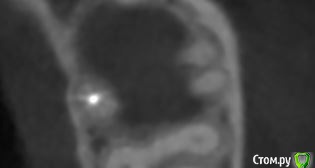

krokomot Опубликовано 19 февраля, 2020 Поделиться Опубликовано 19 февраля, 2020 в медиальном корне недопломбировка и наличие вероятно 4ого канала. Ссылка на комментарий

dmitrib81 Опубликовано 20 февраля, 2020 Автор Поделиться Опубликовано 20 февраля, 2020 Зуб делали много лет назад. Примерно неделю назад появились периодические боли, бывает целый день не болит, потом снова ноющая боль. С приёмом пищи никак не связано. На горячие и холод реакции нетПодскажите, может ещё прислать фоток из КТ Пикассо, а то я в этом ничего не понимаю, просто разных фото экрана прислал, без какого-либо понимания, на что смотреть.. Ссылка на комментарий

dmitrib81 Опубликовано 20 февраля, 2020 Автор Поделиться Опубликовано 20 февраля, 2020 еще фото Ссылка на комментарий